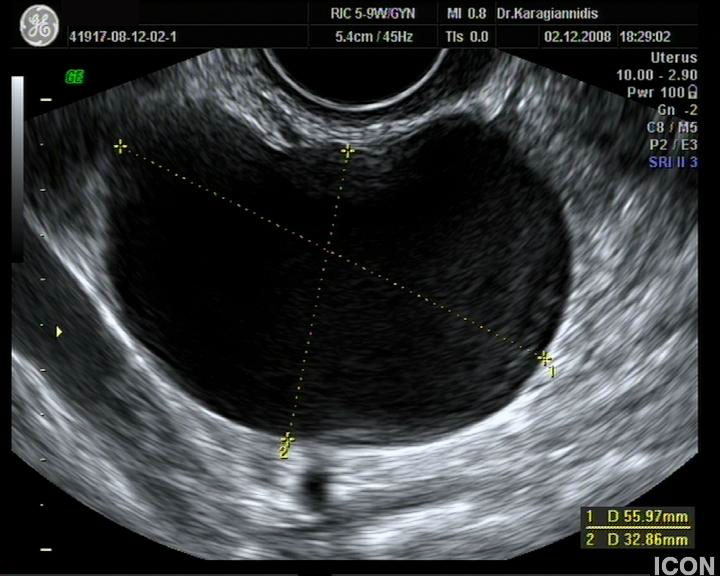

Αυχενική διαφάνεια

Η αυχενική διαφάνεια (ΑΔ) είναι η συλλογή υγρού στον τράχηλο του εμβρύου και συγκεκριμένα ανάμεσα στο δέρμα και στους ιστούς που καλύπτουν τη σπονδυλική στήλη.